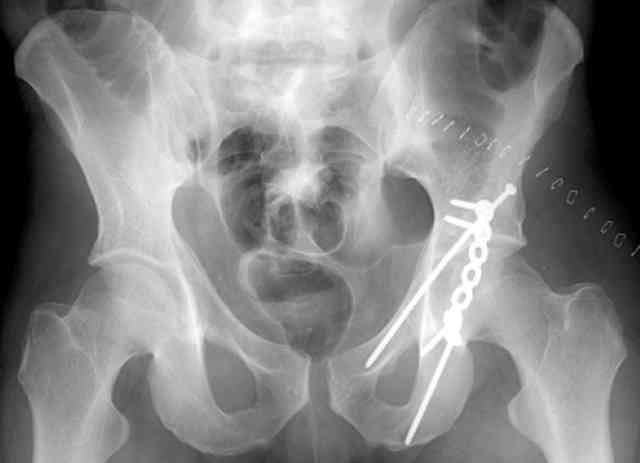

The 2nd example is of a motorcyclist with a transverse fracture-dislocation...he had a closed attempted reduction and placed in traction but the manipulative reduction was not concentric (not unusual for this injury pattern)...so the traction was adjusted to be just enough to disengage the head from the fracture (12#) until he could be cleared for surgery one day after injury...he was treated "urgently" then with a prone KL, clean the fracture, reduce and clamp it, screw it, support with a balanced plate, close, and enjoy...2-3hours, 400cc EBL, blah, blah, blah..